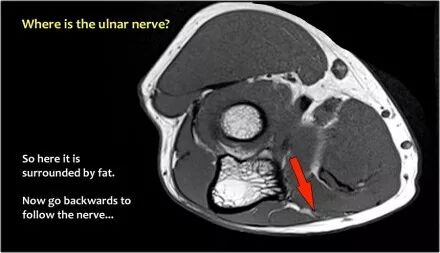

尺神经:在这里,我们看到了肘管内的尺神经。尺骨侧支带的后带形成隧道的底部,而支持带形成屋顶。

该患者有尺神经神经病变。肘管综合征是一种常见的周围神经病变。它产生于肘管内尺神经,其中该神经传递肘管支持带的下方的压缩。

肘管综合征的可能原因● 过度使用● 由于纤维组织中的先天性松弛,尺神经半脱位● 肱骨骨折伴游离体或愈伤组织形成● 由上髁或鹰嘴引起的关节炎● 存在肌肉异常● 软组织肿块:神经节,脂肪瘤,骨软骨瘤,继发于类风湿性关节炎的滑膜炎,感染(例如结核病)和出血。

当他们将尺神经带出隧道时,他们把它放在哪里,它可以是皮下,肌肉下或肌肉内。

因此,当我们回到图像时,您会发现很难找到神经。任何这些皮下结构都可以是转位神经。一种方法是远端跟随结构,直到你发现远端的尺神经位于由脂肪包围的前臂近端的正常位置。然后当你向近端跟随它时,你会发现这是皮下移位。

在这种情况下,有神经炎。神经增大。在T2W图像上有高信号。另一个标志是在矢状图像(箭头)上看到的束的不均匀扩大。